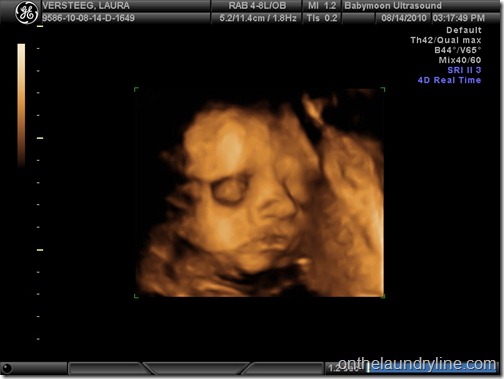

We went for a 3D ultrasound yesterday! It was very cool. The video looks a lot cooler than the pictures and give you a way clearer idea of what baby will look like. A lot like Nicole, actually! Definitely siblings, lol. Quite a chubby pair of cheeks, for 28 weeks, and a very similar nose and face shape overall. We were going to be paying for a bigger package, but since the tech couldn’t get any good pics because baby was ‘either very shy or very stubborn’ (I’m gonna guess stubborn, if Nicole is any indicator) we got the lowest package price they had. We could have come back to try again for free but Chris and I were both willing to bet we wouldn’t have better luck next time. There were two major problems, one being that baby was snuggled up to the placenta and making things difficult (which could change if we tried again) but the bigger one being that baby constantly had one fist in the mouth and the other arm thrown around the head. Chris and I agreed that since Nicole used to sleep with both arms thrown around her head like that when she was a baby, odds were that this little one would have that same pose next time too. Especially as things are getting too crowded for gymnastics.

Anyways, here is a sneak peak! (minus the gender shots, we’re keeping that under wraps!)

eye open, sucking on fist

chubby little cheeks! Considering at 28 weeks babies have very little fat on their little bodies, lol. At this stage baby weighs about 2lbs!